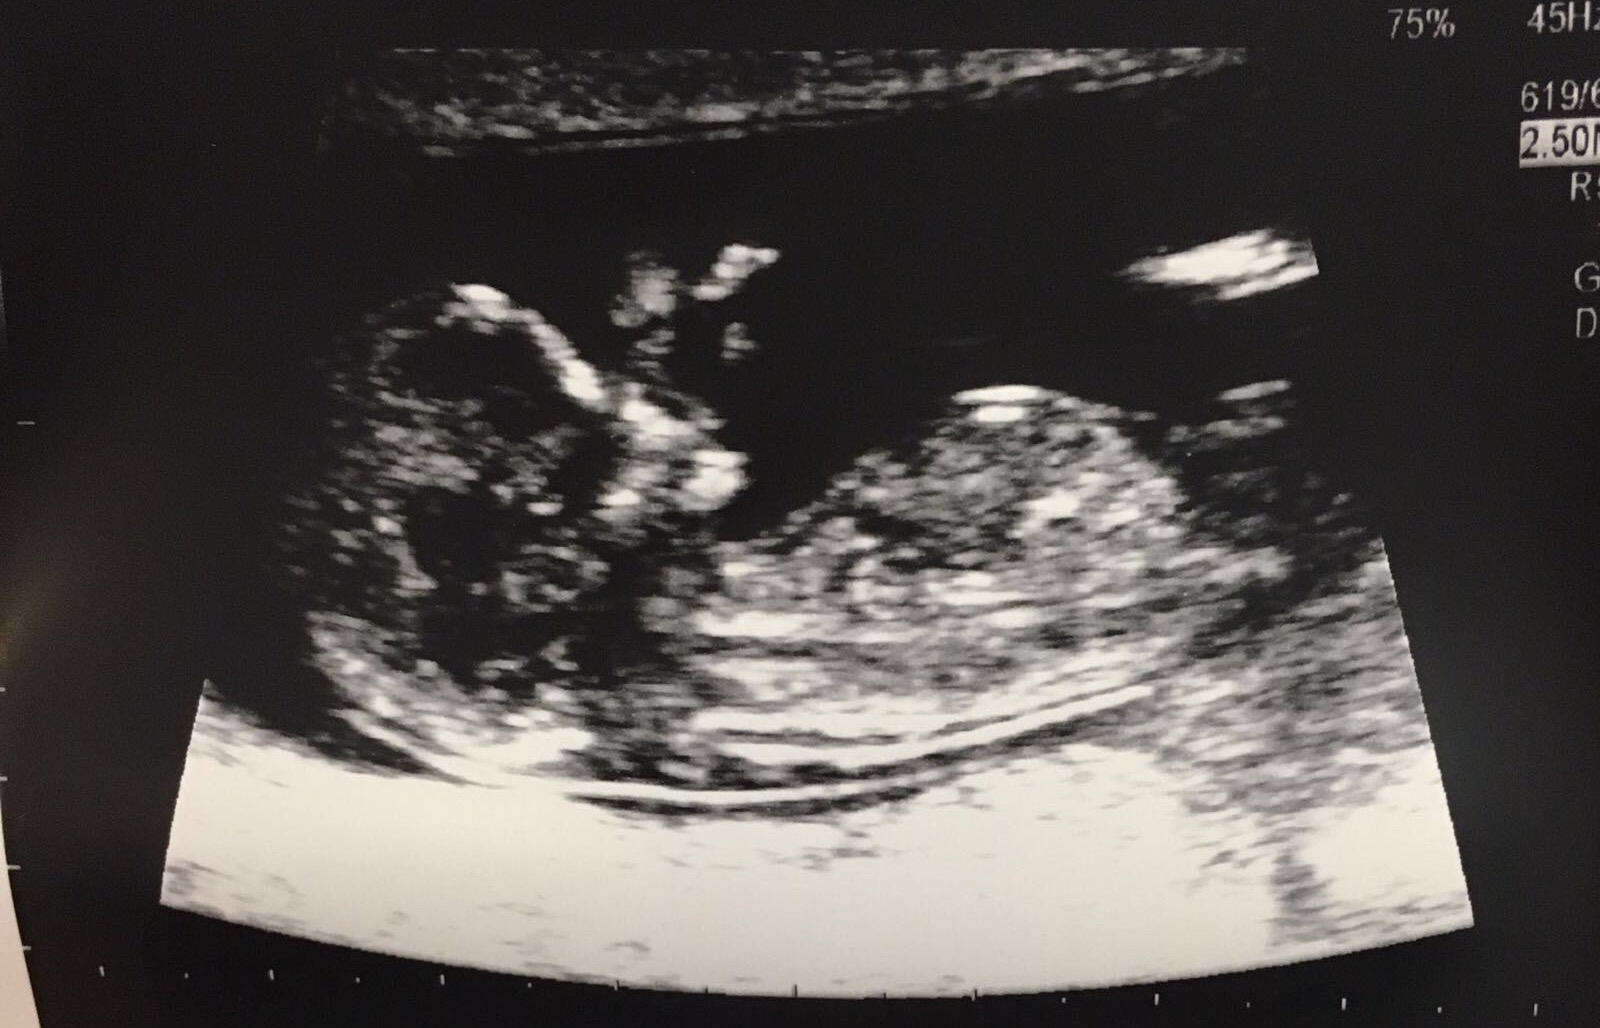

Hi ladies, I just had my 12 weeks 3 days first ultrasound scan today. It was very exciting to see the heart beating and the baby move, got the picture, but I can hardly guess anything - the sonographer said it is a very good picture! Any predictions? :happy:

Attachment 31987